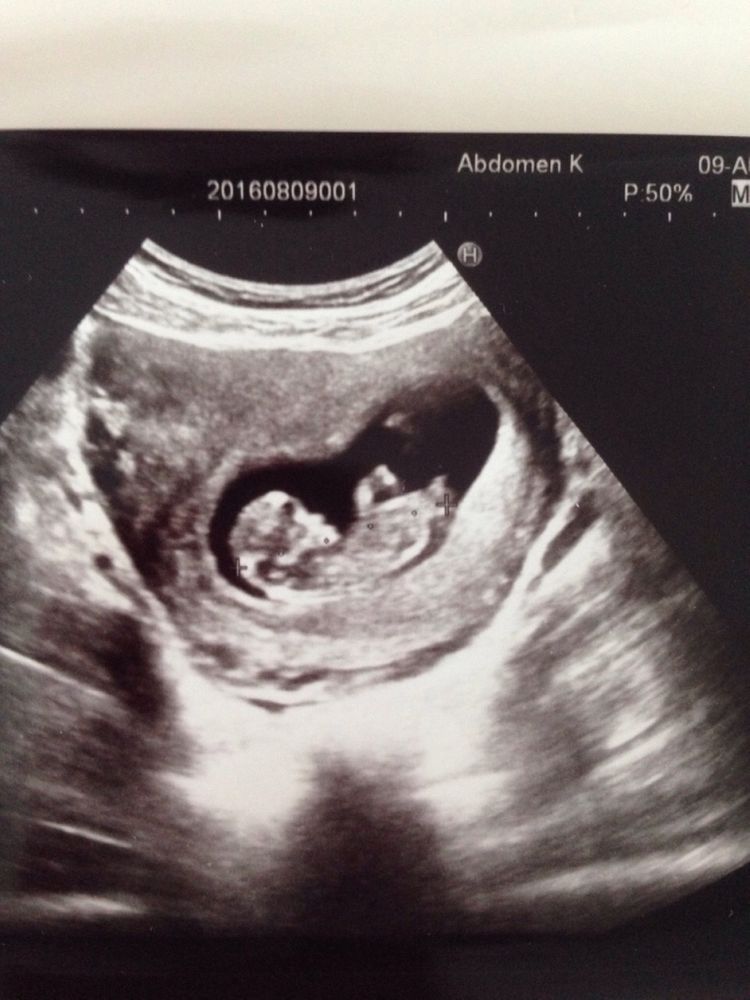

Ну шо девчонки) не оставляет меня в покое пол моего малыша)))была на скрининге, фото не дают, но выбила видео😌так вот..муж сфотал первое фото вчера в почте выкладывала, бугорок на девочку смахивает, сегодня пересматривала видео и вот что промелькнуло🤔на 2 фото, еле словила😬так что скорее будет мальчишка)очень интересная тема на самом деле с этими бугорками😅иии вопрос, в 15 недель хорошо уже должно быть видно писюшку?

Мальчик у вас.Второе фото-строго саггитальный срез, поэтому оно информативней...

То, что на втором фото это тоже девочка, только тут у неё попа закинута не много. У меня так же было с 6 дочкой. Вот наше фото